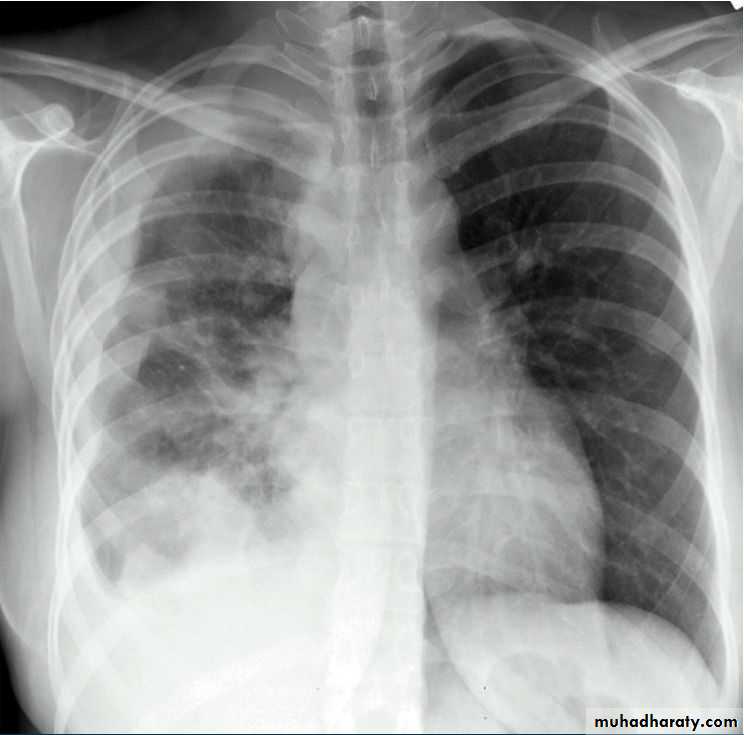

Patient with fever, rigor and dyspnea